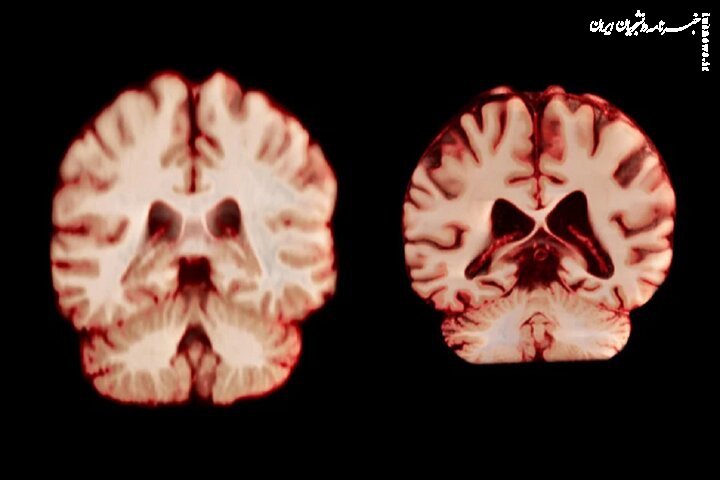

راوندال اضافه میکند که تحقیقات قبلی که تفاوتهای جنسیتی در پیری مغز را بررسی میکردند، نتایج متفاوتی را نشان دادهاند. چندین مطالعه نشان دادهاند که مردان در مقایسه با زنان، کاهش بیشتری در کل ماده خاکستری و اندازه هیپوکامپ را تجربه میکنند، در حالی که سایر تحقیقات، کاهش شدیدتر ماده خاکستری در زنان را گزارش کردهاند.

جدیدترین مطالعه شامل بیش از ۱۲ هزار و ۵۰۰ اسکن مغزی تصویربرداری تشدید مغناطیسی (MRI) از ۴۷۲۶ نفر بود که حداقل دو اسکن برای هر نفر، با فاصله متوسط سه سال انجام شده بود که به بیماری آلزایمر یا هرگونه اختلال شناختی مبتلا نبودند و به عنوان شرکتکننده کنترل در ۱۴ مجموعه داده بزرگتر قرار داشتند. محققان با بررسی عواملی از جمله ضخامت ماده خاکستری و اندازه نواحی مرتبط با بیماری آلزایمر، مانند هیپوکامپ که برای حافظه ضروری است، نحوه تغییر ساختار مغز افراد را در طول زمان مقایسه کردند.

به طور کلی، مردان در مقایسه با زنان، کاهش حجم بیشتری را در مناطق بیشتری از مغز تجربه کردند. به عنوان مثال، قشر پس مرکزی که مسئول پردازش احساسات لامسه، درد و دما و همچنین موقعیت و حرکات بدن است، در مردان سالانه ۲.۰ درصد و در زنان سالانه ۱.۲ درصد کاهش یافت.